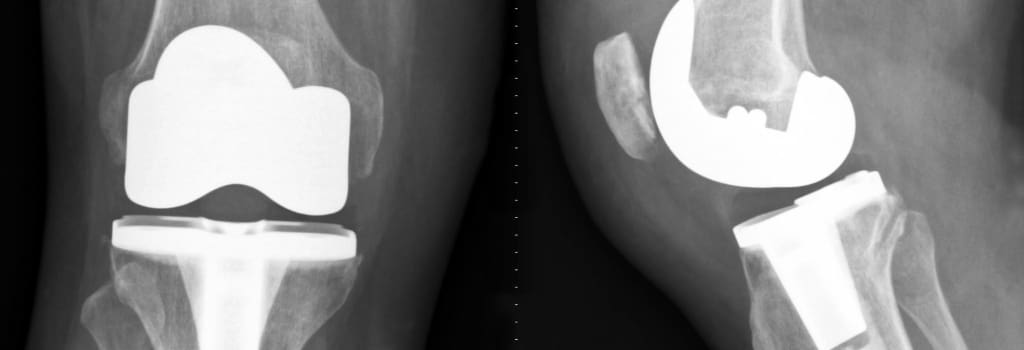

Metal-on-metal implants grew in popularity during the early 2000s. Although promoted as more durable than their counterparts, metal-on-metal implants have resulted in numerous complications, including loosening and dislocation, as well as pain.

More specifically, metal-on-metal implants can shed microscopic metallic elements, including cobalt and chromium, which can enter the bloodstream, leading to metallosis. According to the FDA, the metal ball and metal cup that comprises the metal-on-metal implant will slide against one another while walking or running, causing the release of metallic particles.